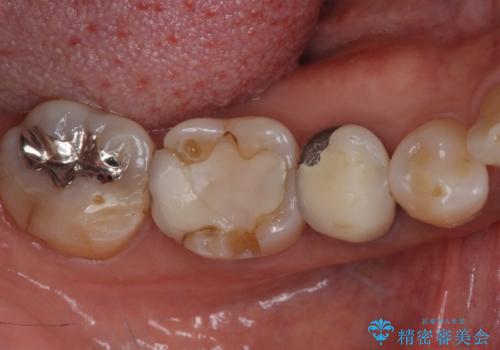

- セラミックが剥がれたり、歯質が欠けたりした奥歯を気にして来院された患者様です。

咬合力が強い方であったため、2歯をフルジルコニアクラウンにて補綴することとしました。